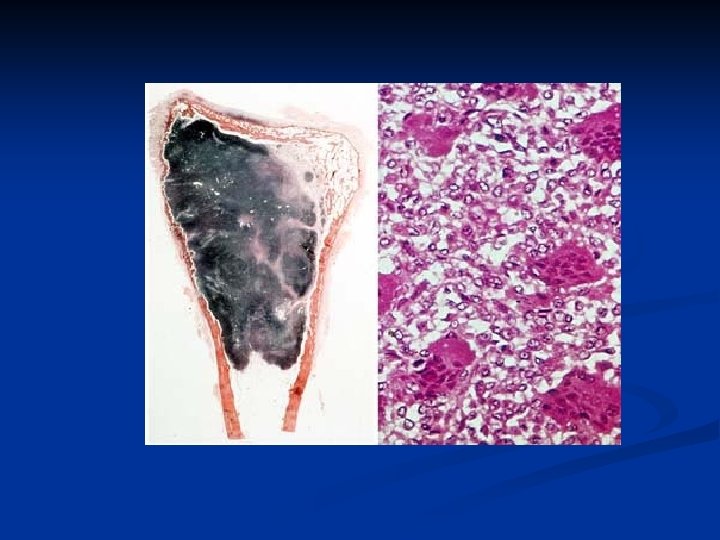

Giant Cell Tumor An aggressive benign tumor n Composed of : n well vascularized stroma n plump, spindly, and oval tumor cells n multinucleated tumor giant cells n n Over the age of 20: most commonly in the third decade of life n slight female preponderance n

n The skeletal location: n 50% of cases occur near the knee n most commonly in the distal end of the femur or the upper end of the tibia. n The x-ray picture : Large, eccentric, oval, n Radioluscent destructive lesion centered in the epiphysis, n Cortical erosion and thinning, n Expanding the bone contours without a border. n

Giant Cell Tumor

Giant Cell Tumor